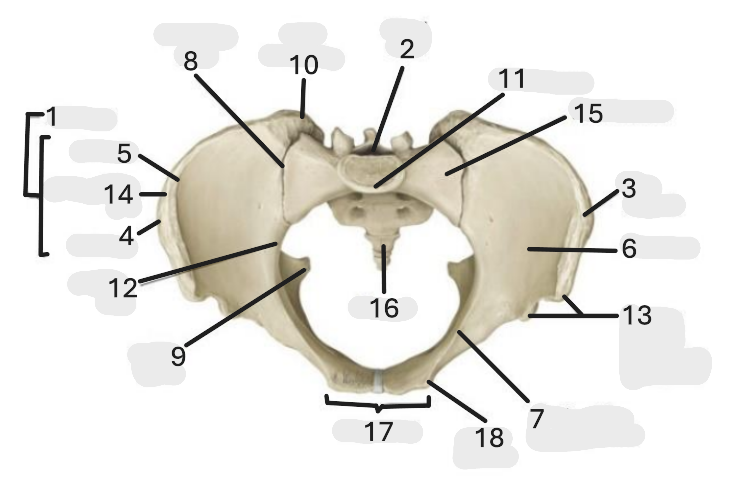

Where is the pelvic inlet

1

Where is the sacro-iliac joint

2

Where is the pubic tubercle

3

Where are the S1 body

4

Where is the ischial spine

5

Where is the ala of sacrum

6

Where is the anterior superior iliac spine

7

Where is the ischiopubic ramus

8

Where is the coccyx

9

Where is the obturator foramen

10

Where is the pubic symphysis

11

Where is the ischial tuberosity

12